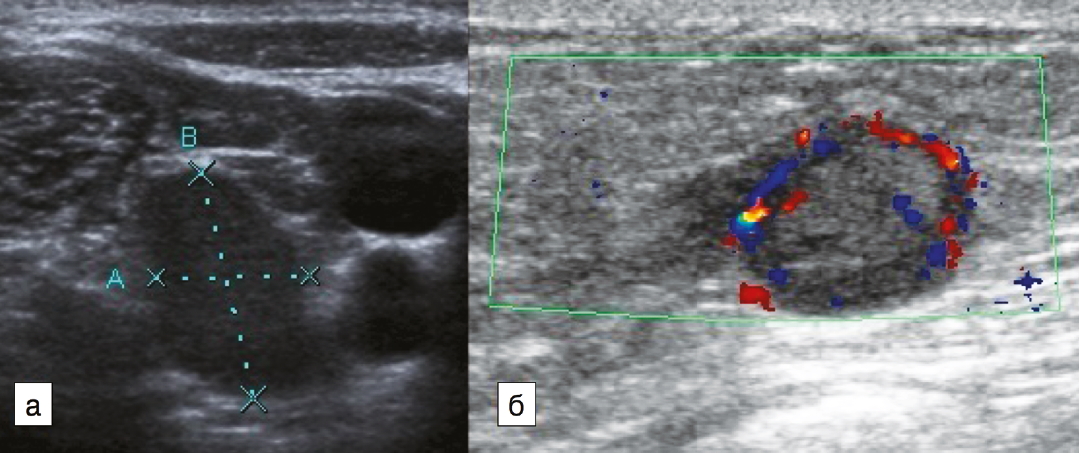

Наиболее удобным, доступным и хорошо изученным методом оценки статуса регионарных лимфатических узлов является УЗИ, при котором возможно оценить форму, контуры и структуру измененных лимфатических узлов. Для метастатических изменений характерна округлая и неправильная форма лимфатического узла (встречаются в 79% наблюдений); рис. 1. Также могут выявляться метастазы в лимфатических узлах с измененным корковым слоем, который проявляется его неравномерным утолщением или выбуханием контура на отдельном участке (рис. 2). Структура метастатически измененных лимфатических узлов многообразна и может быть гипоэхогенной, анэхогенной, гиперэхогенной, гетерогенной, с кальцинатами и даже с включениями жидкостного характера (рис. 3).

Рис. 1. Метастатические изменения регионарных лимфатических узлов в В-режиме: а – измененный надключичный лимфатический узел неправильной формы; б – измененный округлый подмышечный лимфатический узел.

Fig. 1. B-mode ultrasound images of regional lymph node metastases: a – abnormal supraclavicular lymph node with an irregular shape; b – abnormal round axillary lymph node.

При цветовом и энергетическом допплеровском картировании кровоток в метастатически измененных лимфатических узлах визуализируется в 93% наблюдений. При этом выявляются извитые, разнокалиберные, ветвистые, хаотично расположенные сосуды (рис. 4).

Рис. 4. Энергетическое допплеровское картирование подмышечного лимфатического узла с метастатическими изменениями.

Fig. 4. Color Doppler Energy Mapping of metastatic axillary lymph node.